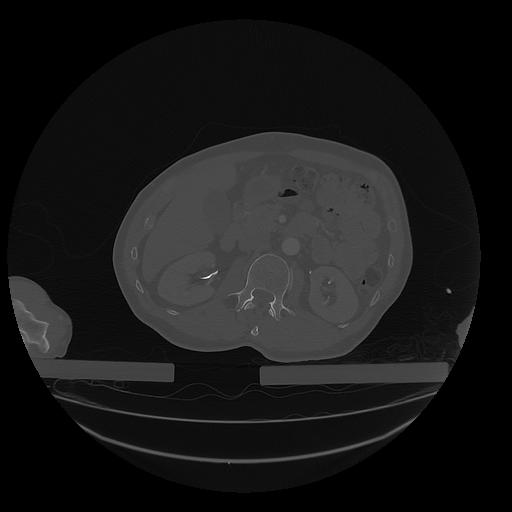

31 PULMON,CE,Vol,1.0,PULMON,,